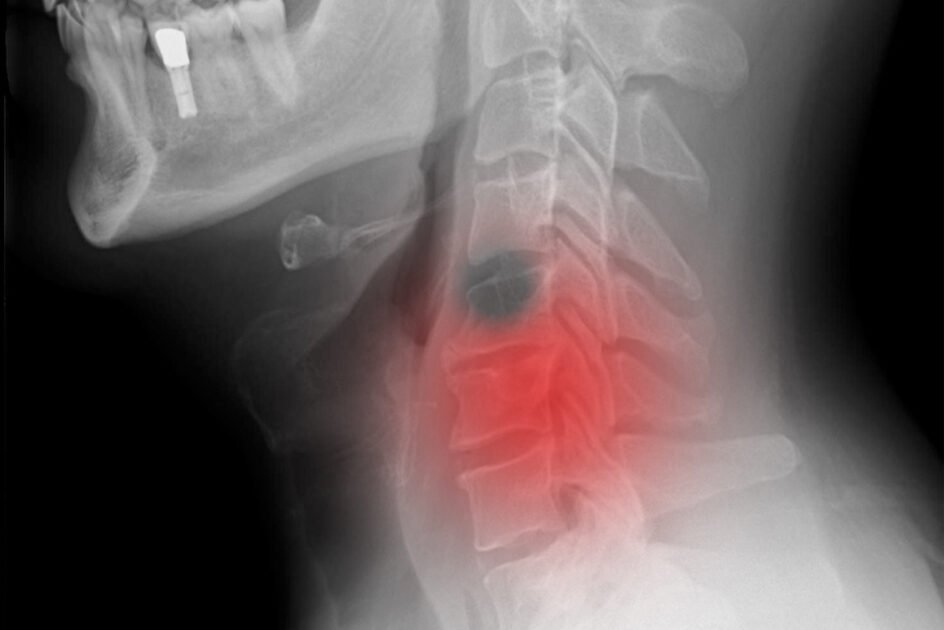

اسلام آباد (نیوز ڈیسک )سر اور گردن کاکینسر ، کینسر کے تمام معاملات کا 6فیصد ہوتے ہیں۔ ان کا آغاز منہ ، ناک ، تنفس کی نالیوں ، آواز کے غدود اور حلق سے ہوتاہے۔ یہ اکثر جارحانہ نوعیت کے مزید پڑھیں